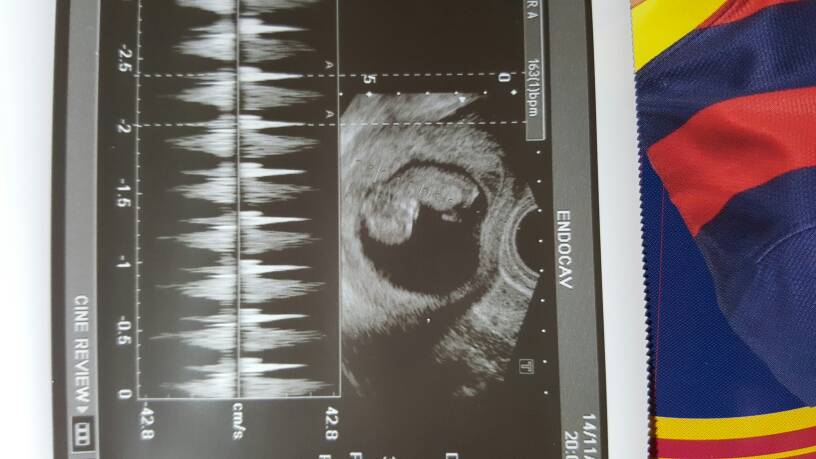

Pani doktor otoczyła mnie przecudowna opieką. Bobasek wcale nie jest aż tyle młodszy - tamten lekarz miał gorszy sprzęt. Dziś miał na usg 10t6d. Miał 4 cm i 160 uderzen serca na minute

Zobacz załącznik 782848